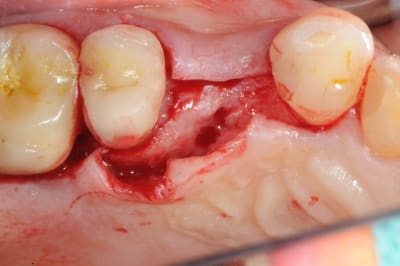

pour débuter ce post je propose un petit cas avec une ROG un comblement alvéolaire et un lambeau pédiculé pour fermer le site d'extraction.

au début incision supra crestal puis lambeau muco-périosté.

avec une simple lame 11 qui tranche le long de gencive palatine. évidemment c'est le plus dure à faire pour éviter de transpercer ou d'avoir d'un coté ou de l'autre une épaisseur trop faible.